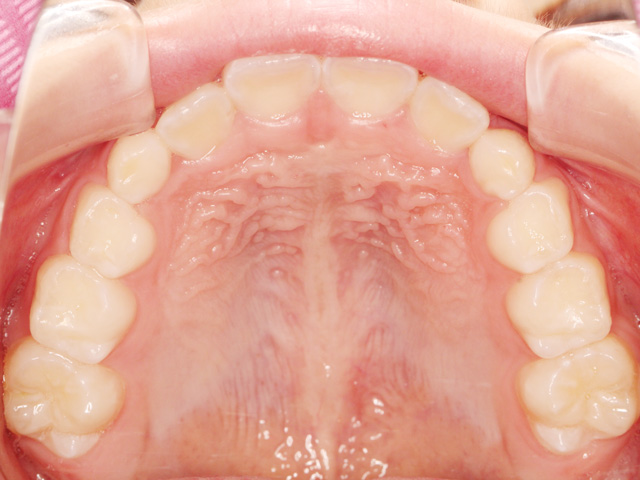

永久歯がすべて生え揃ってから行う大人の矯正とは異なり、顎の成長をコントロールしながら、歯が正しく並ぶための土台を整えていくのが特徴です。

歯並びを改善させるだけでなく、それと同時に生え変わっていない永久歯が、将来並ぶスペースを確保したり、上下の顎のバランスを整えたりします。

第一期治療を完了した全てのケースが第二期治療まで必要になるわけではありません。第一期治療だけで十分なケースも少なくありません。